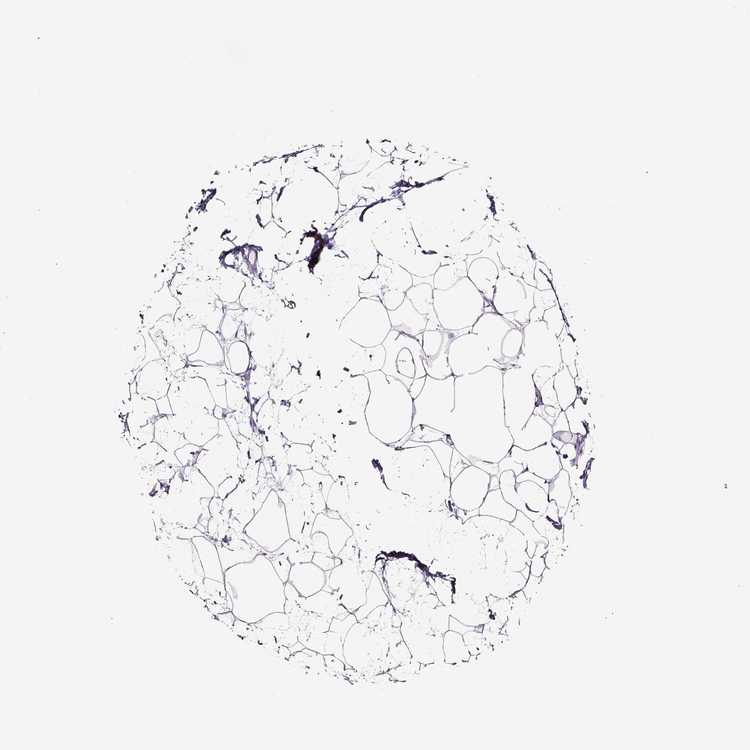

BREAST - Antibody stainingi

Antibody staining in the annotated cell types in the current human tissue is reported as not detected, low, medium, or high, based on conventional immunohistochemistry profiling in selected tissues. This score is based on the combination of the staining intensity and fraction of stained cells.

Each image is clickable and will lead to virtual microscopy that enables deeper exploration of all samples and also displays staining intensity scores, fraction scores and subcellular localization as well as patient and tissue information for each sample.

Antibody HPA071861

Adipocytes Not detected

Glandular cells Not detected

Myoepithelial cells Not detected